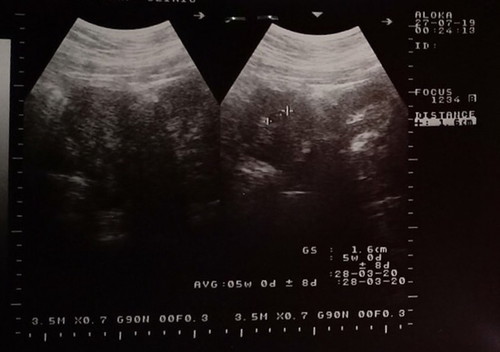

รูปแรกเมื่อวันที่ 27 ก.ค 62 5 w รูปสองเมื่อวาน 16 ส.ค 62 7w 6d แต่ใบภาพอันตาซาวเป็น 7 w 4d มีผลอะไรไหมคะ

เครื่องซาว์นับอายุครรภ์ตามขนาดของเด็กค่ะ มีสิทธิ์ที่กำหนดคลอดหรืออายุครรภ์จะเปลี่ยนแปลงได้ตลอด ในทางปฏิบัติคุณหมอจะยึดกำหนดคลอดผลซาวด์แรกเป็นหลักนะคะ จะคลอดตอนไหนให้บวกลบ 2w (เราถามคุณหมอมาค่ะ เพราะเราเคยเข้าใจผิดว่ายึดวันคลอดตามผลซาวด์ล่าสุด จริงๆวันคลอดให้ยึดตามผลซาวด์แรก ส่วนรายละเอียดอื่นๆให้ยึดตามผลซาวด์ล่าสุดค่ะ)